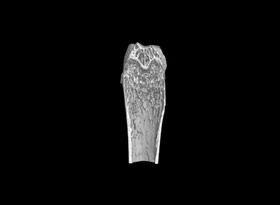

用于骨質(zhì)疏松和關(guān)節(jié)炎動物模型潛伏期的骨結(jié)構(gòu)和密度改變的研究。MicroCT是目前研究骨立體結(jié)構(gòu)、容量和微結(jié)構(gòu)細微改變較好方法。

1骨組織樣本掃描。

2提供2D圖、3D圖和相關(guān)參數(shù)的分析數(shù)據(jù)(骨密度BMD 單獨收費)。